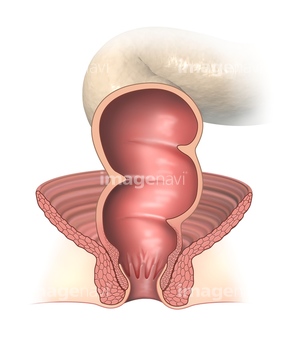

身体 腹部 直腸 結腸 生物学 理科 断面 の画像素材 写真素材ならイメージナビ

肛門 直腸 生殖器 筋肉 人体解剖学 生物学 断面 の画像素材 写真素材ならイメージナビ

直腸 肛門 断面 の画像素材 医療 イラスト Cgの写真素材ならイメージナビ

身体 腹部 直腸 結腸 生物学 理科 断面 の画像素材 写真素材ならイメージナビ

肛門 直腸の構造断面図イラスト 人体 医療 イメージマート

下部直腸の構成図 mサイズ Laiman Stockweb メディカルイラスト素材のダウンロード販売

直腸 肛門 断面 の画像素材 医療 イラスト Cgの写真素材ならイメージナビ

身体 腹部 肛門 直腸 人体解剖学 生物学 断面 の画像素材 イラスト素材ならイメージナビ